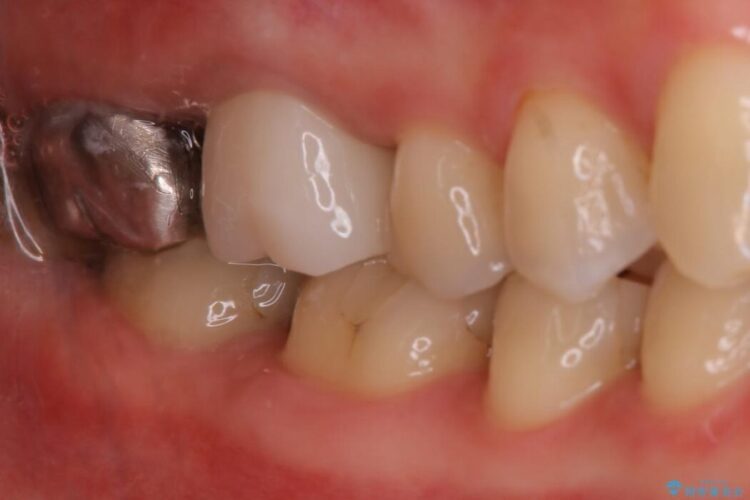

X線画像を診断すると、充填不良の根管の先に透過像が認められたため、再根管治療をご提案いたしました。

根管治療を再度行うことでフィステル(ニキビのようなできもの)は消失しました。

最終的にセラミッククラウンによる補綴治療を行いました。